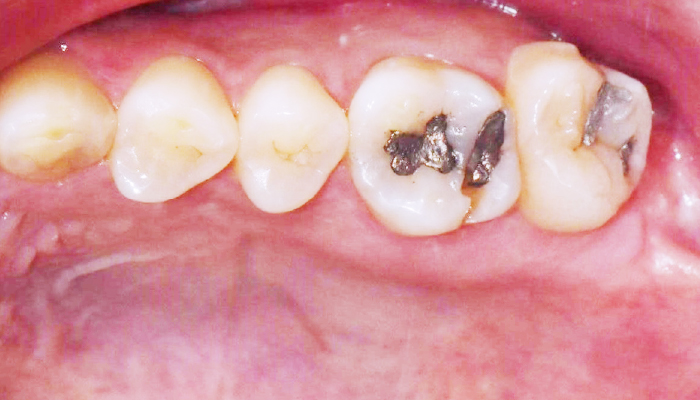

이갈이는 다양한 원인에 의해 발생되는 것으로 치아의 마모, 턱관절 통증, 두통 등을 유발합니다. 치과치료와 함께 생활습관을 교정하는 방법으로 이갈이를 줄여나갈 수 있습니다.

다양한 합병증을 동반하는 이갈이